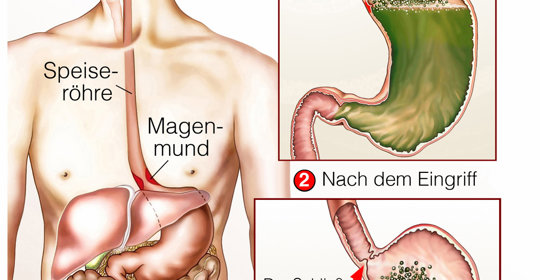

胃食道逆流患者可以吃生花生,但要注意適量。胃食道逆流是一種常見的消化系統疾病,是指胃內容物逆流至食道引起的一種症狀或併發症。

胃食道逆流患者可以吃水果,但需要適量。胃食道逆流是指胃內容物和十二指腸液等逆流入食道引起的臨床症狀及併發症。